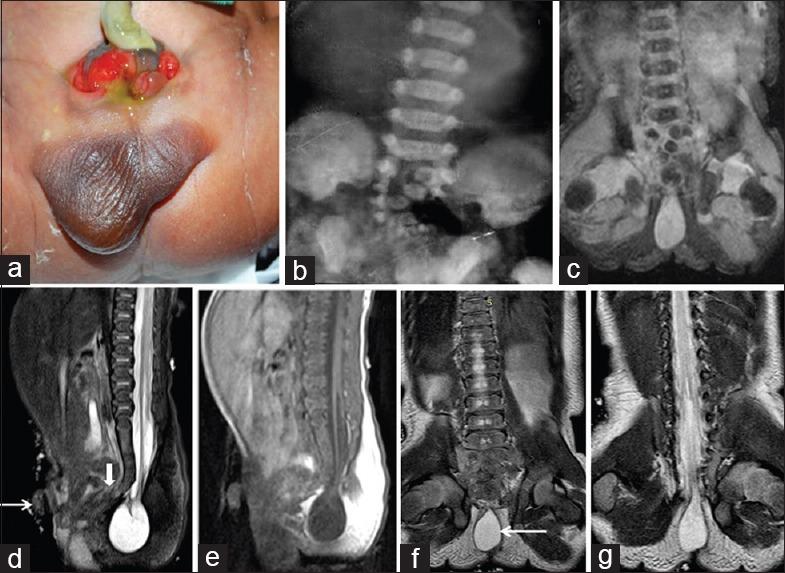

In our study, 21 pediatric patients were diagnosed with sacral agenesis/dysgenesis related to CRS. According to the Pang's classification, 2 (9.5%) patients were Type I, 5 (23.8%) patients were Type III, 7 (33.3%) patients were Type IV, and 7 (33.3%) patients were of Type V CRS. Clinically, 17 (81%) patients presented with urinary incontinence, 6 (28.6%) with fecal incontinence, 9 patients (42.9%) had poor gluteal musculatures and shallow intergluteal cleft, 7 (33.3%) patients had associated subcutaneous mass over spine, and 6 (28.6%) patients presented with distal leg muscle atrophy. MRI showed wedge-shaped conus termination in 5 (23.8%) patients and bulbous conus termination in 3 (14.3%) patients above the L1 vertebral level falling into Group 1 CRS while 7 (33.3%) patients had tethered cord and 6 (28.6%) patients had stretched conus falling into Group 2 CRS.

在我们的研究中,21例小儿患者被诊断为与CRS相关的骶骨发育不全/发育异常。根据庞氏分类,2例(9.5%)患者为I型,5例(23.8%)患者为III型,7例(33.3%)患者为IV型,7例(33.3%)患者为V型CRS。临床上,17例(81%)患者出现尿失禁,6例(28.6%)出现大便失禁,9例(42.9%)患者臀肌发育不良且臀间裂浅,7例(33.3%)患者脊柱上方有皮下肿块,6例(28.6%)患者出现小腿远端肌肉萎缩。MRI显示,5例(23.8%)患者在L1椎体水平以上出现楔形圆锥终丝,3例(14.3%)患者出现球茎状圆锥终丝,属于1组CRS;7例(33.3%)患者有脊髓栓系,6例(28.6%)患者有圆锥拉长,属于2组CRS。